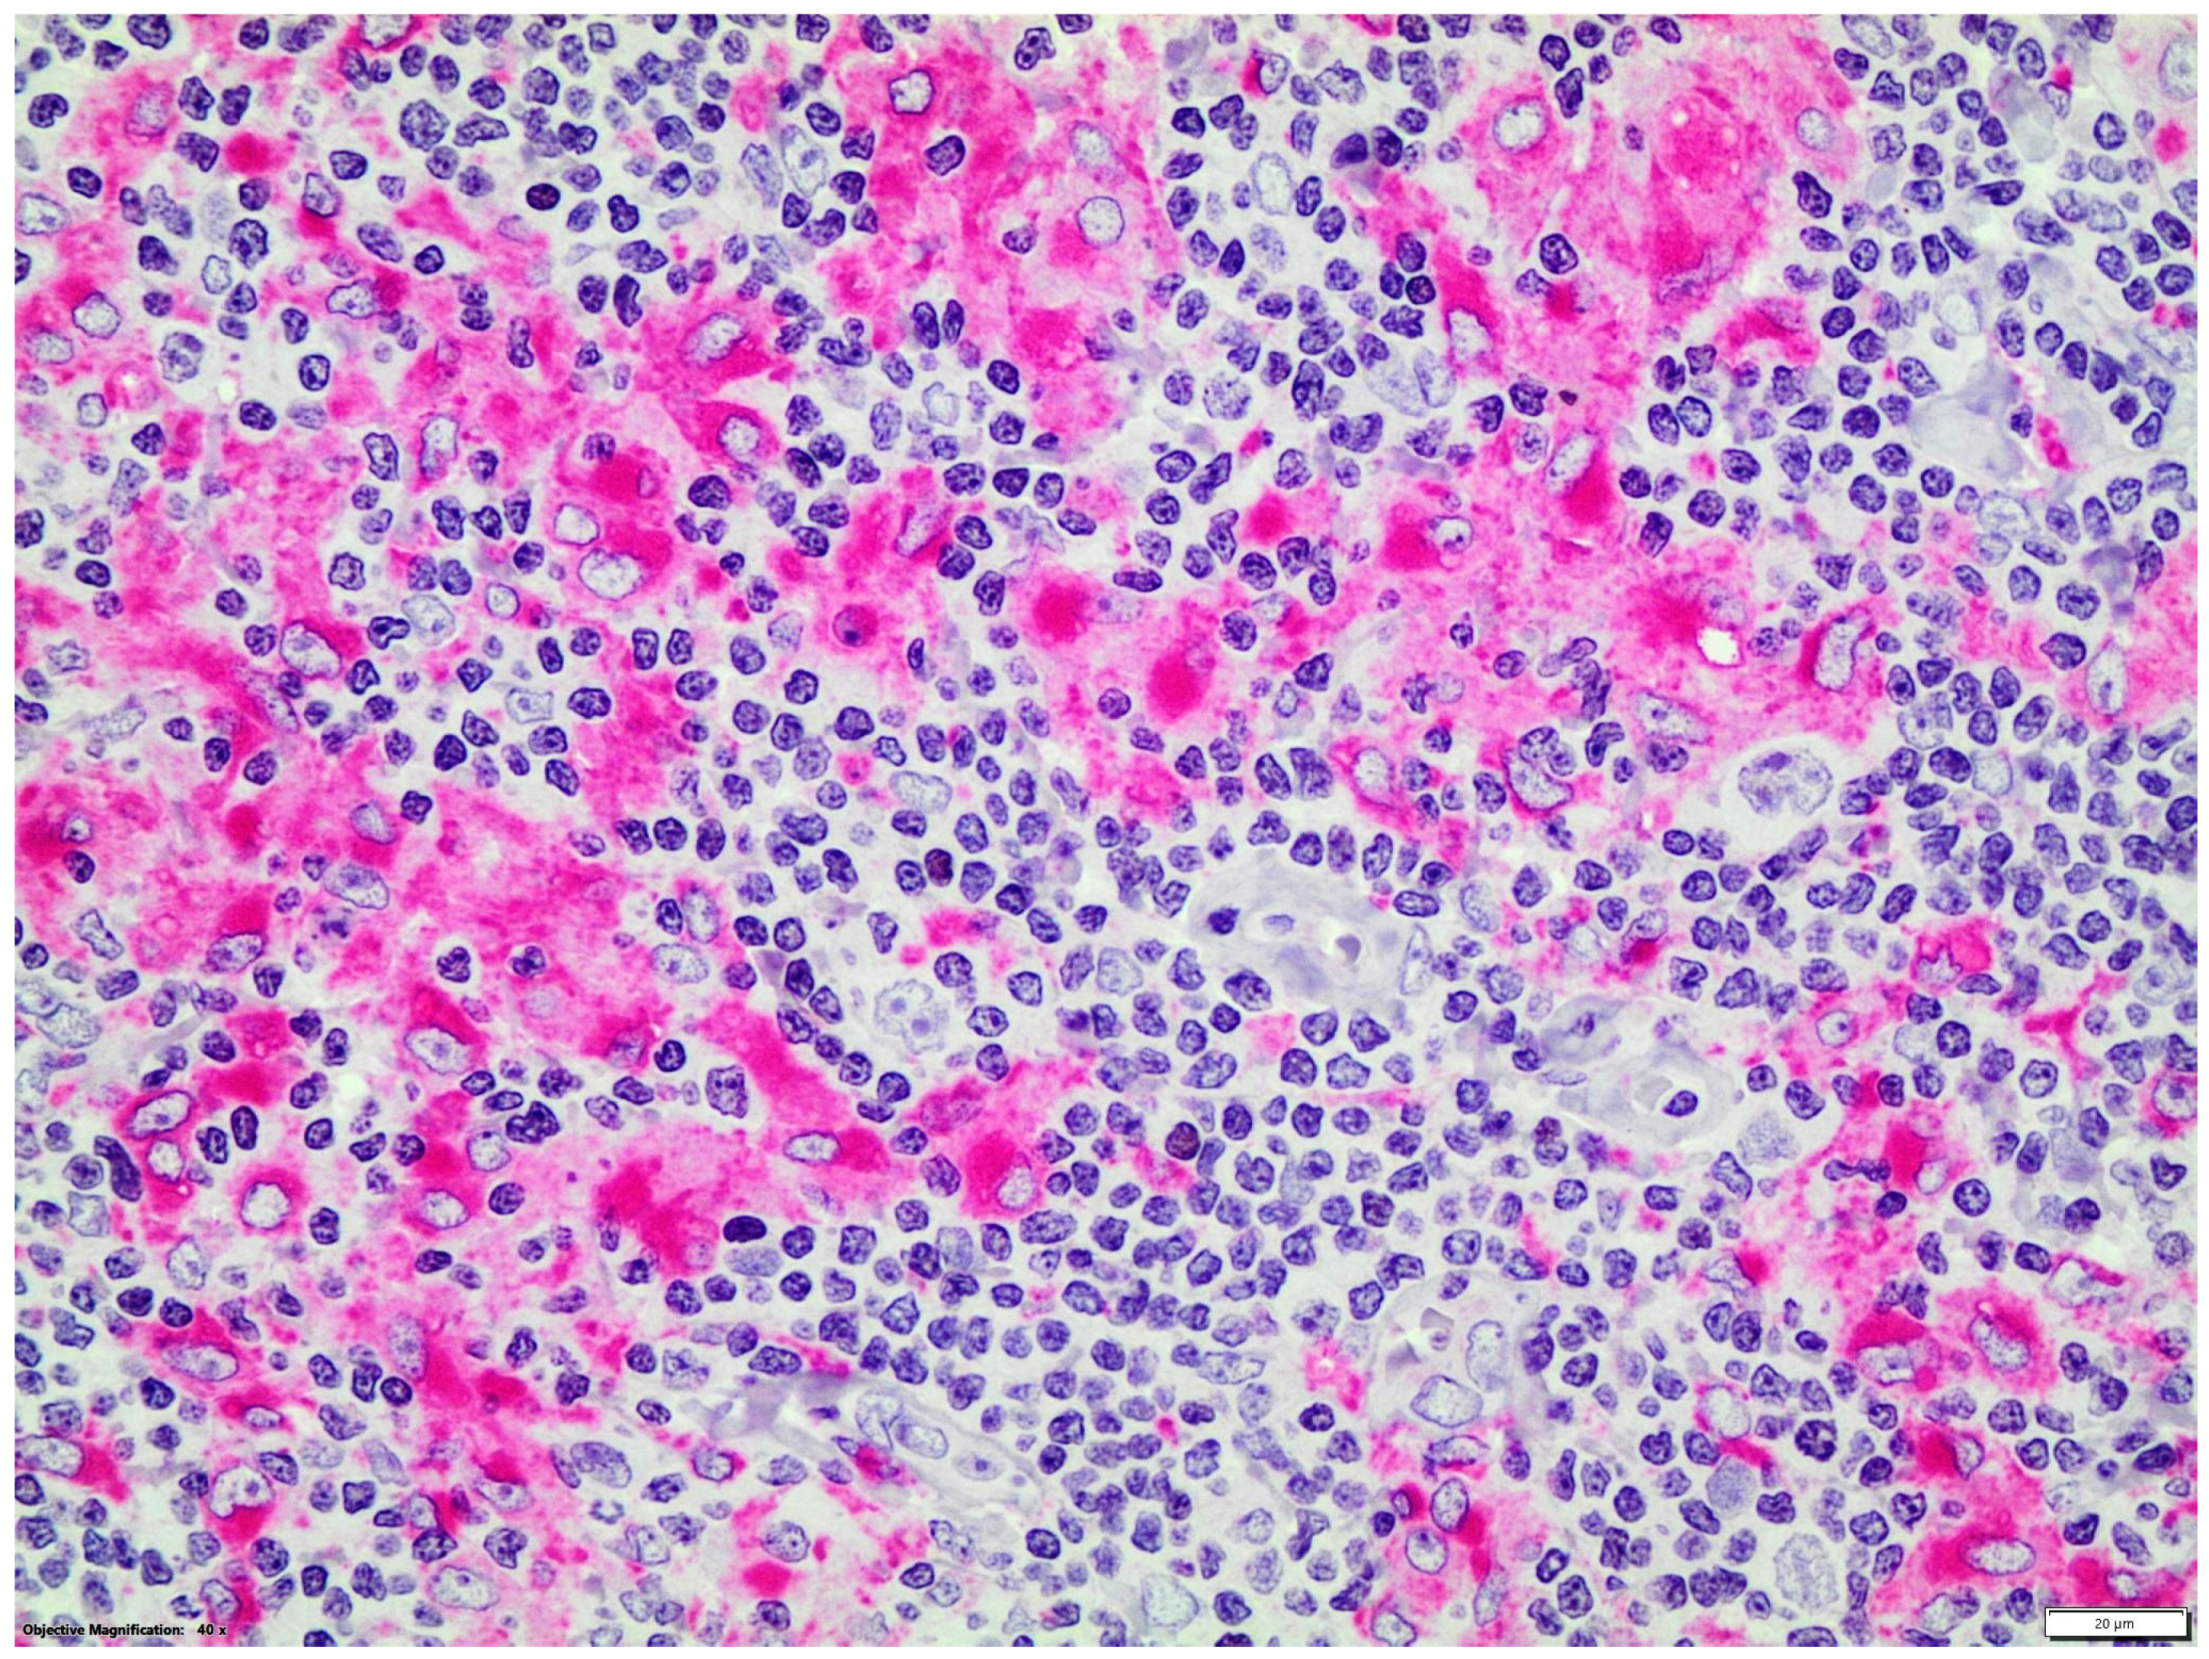

Double immunostainings showed that nuclear GATA3 was expressed by some CD30+ or CD15+ HRS cells and by a few CD3+ T-cells which were frequently organized as small groups, distant from HRS cells. GATA3 nuclear expression was not detected in CD20, CD56 or CD68 + cells (Figure 2 and Figure 3).

Figure 3.

Double LSAB/APAAP immunohistochemical procedure: CD68+ (red staining)/GATA3- macrophages (magnification ×400).